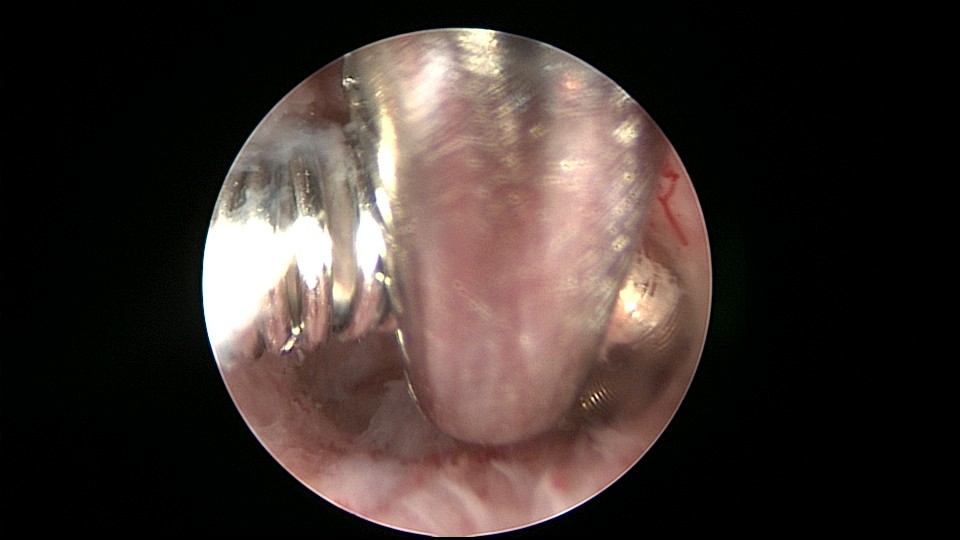

患者51岁,G4P3,顺产3次,闭经半年,外院B超提示有2个环。反复追问病史,还原宫内双环情况,24年前最后一次妊娠可能为带环受孕,行人流术,环未取出(医生和病人不知道有环),随即再次放环一枚。宫腔镜见母体乐环位置下移,纵臂卡在宫颈管内,宫腔镜难以进入宫腔,异物钳先取出母体乐。宫腔内见另一O型环,与右侧宫壁广泛嵌顿,异物钳、取环钩配合中弯钳拉出节育环,环完整,扭曲变形,宫壁见节育环割裂痕迹,宫腔无其他异常。